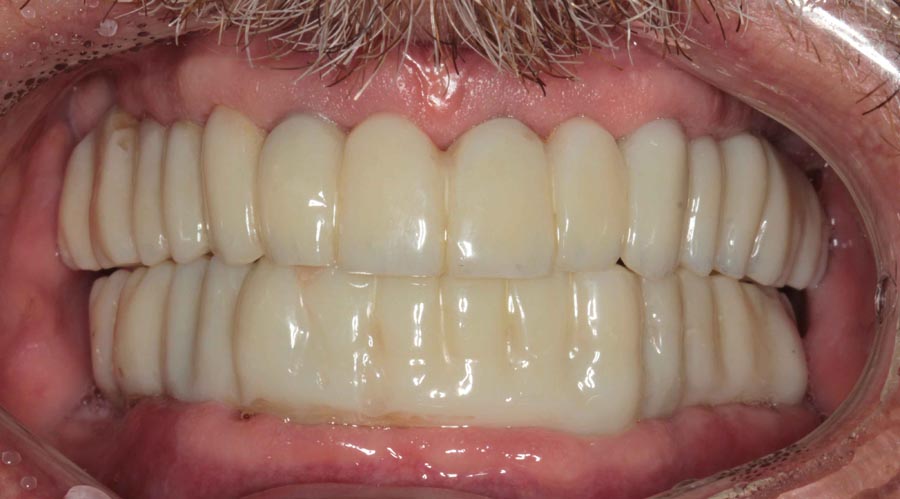

Smile GalleryImplant RestorationsFull Mouth Implant Restoration 1 of 13 Pre-operative smile Pre-operative smile Pre-operative frontal view, lips retracted Pre-operative panoramic image (note bone levels) Post-surgical panoramic image Surgical temporary bridge (note convex contours) Delivery of surgical temporary bridges in both upper and lower Two weeks post-op surgery and temporaries (note amazing tissue response) Three months post- surgery. (Note tissue development) Definitive implant bridges (FP-2) Post-treatment panoramic image Final result smile Final result smile